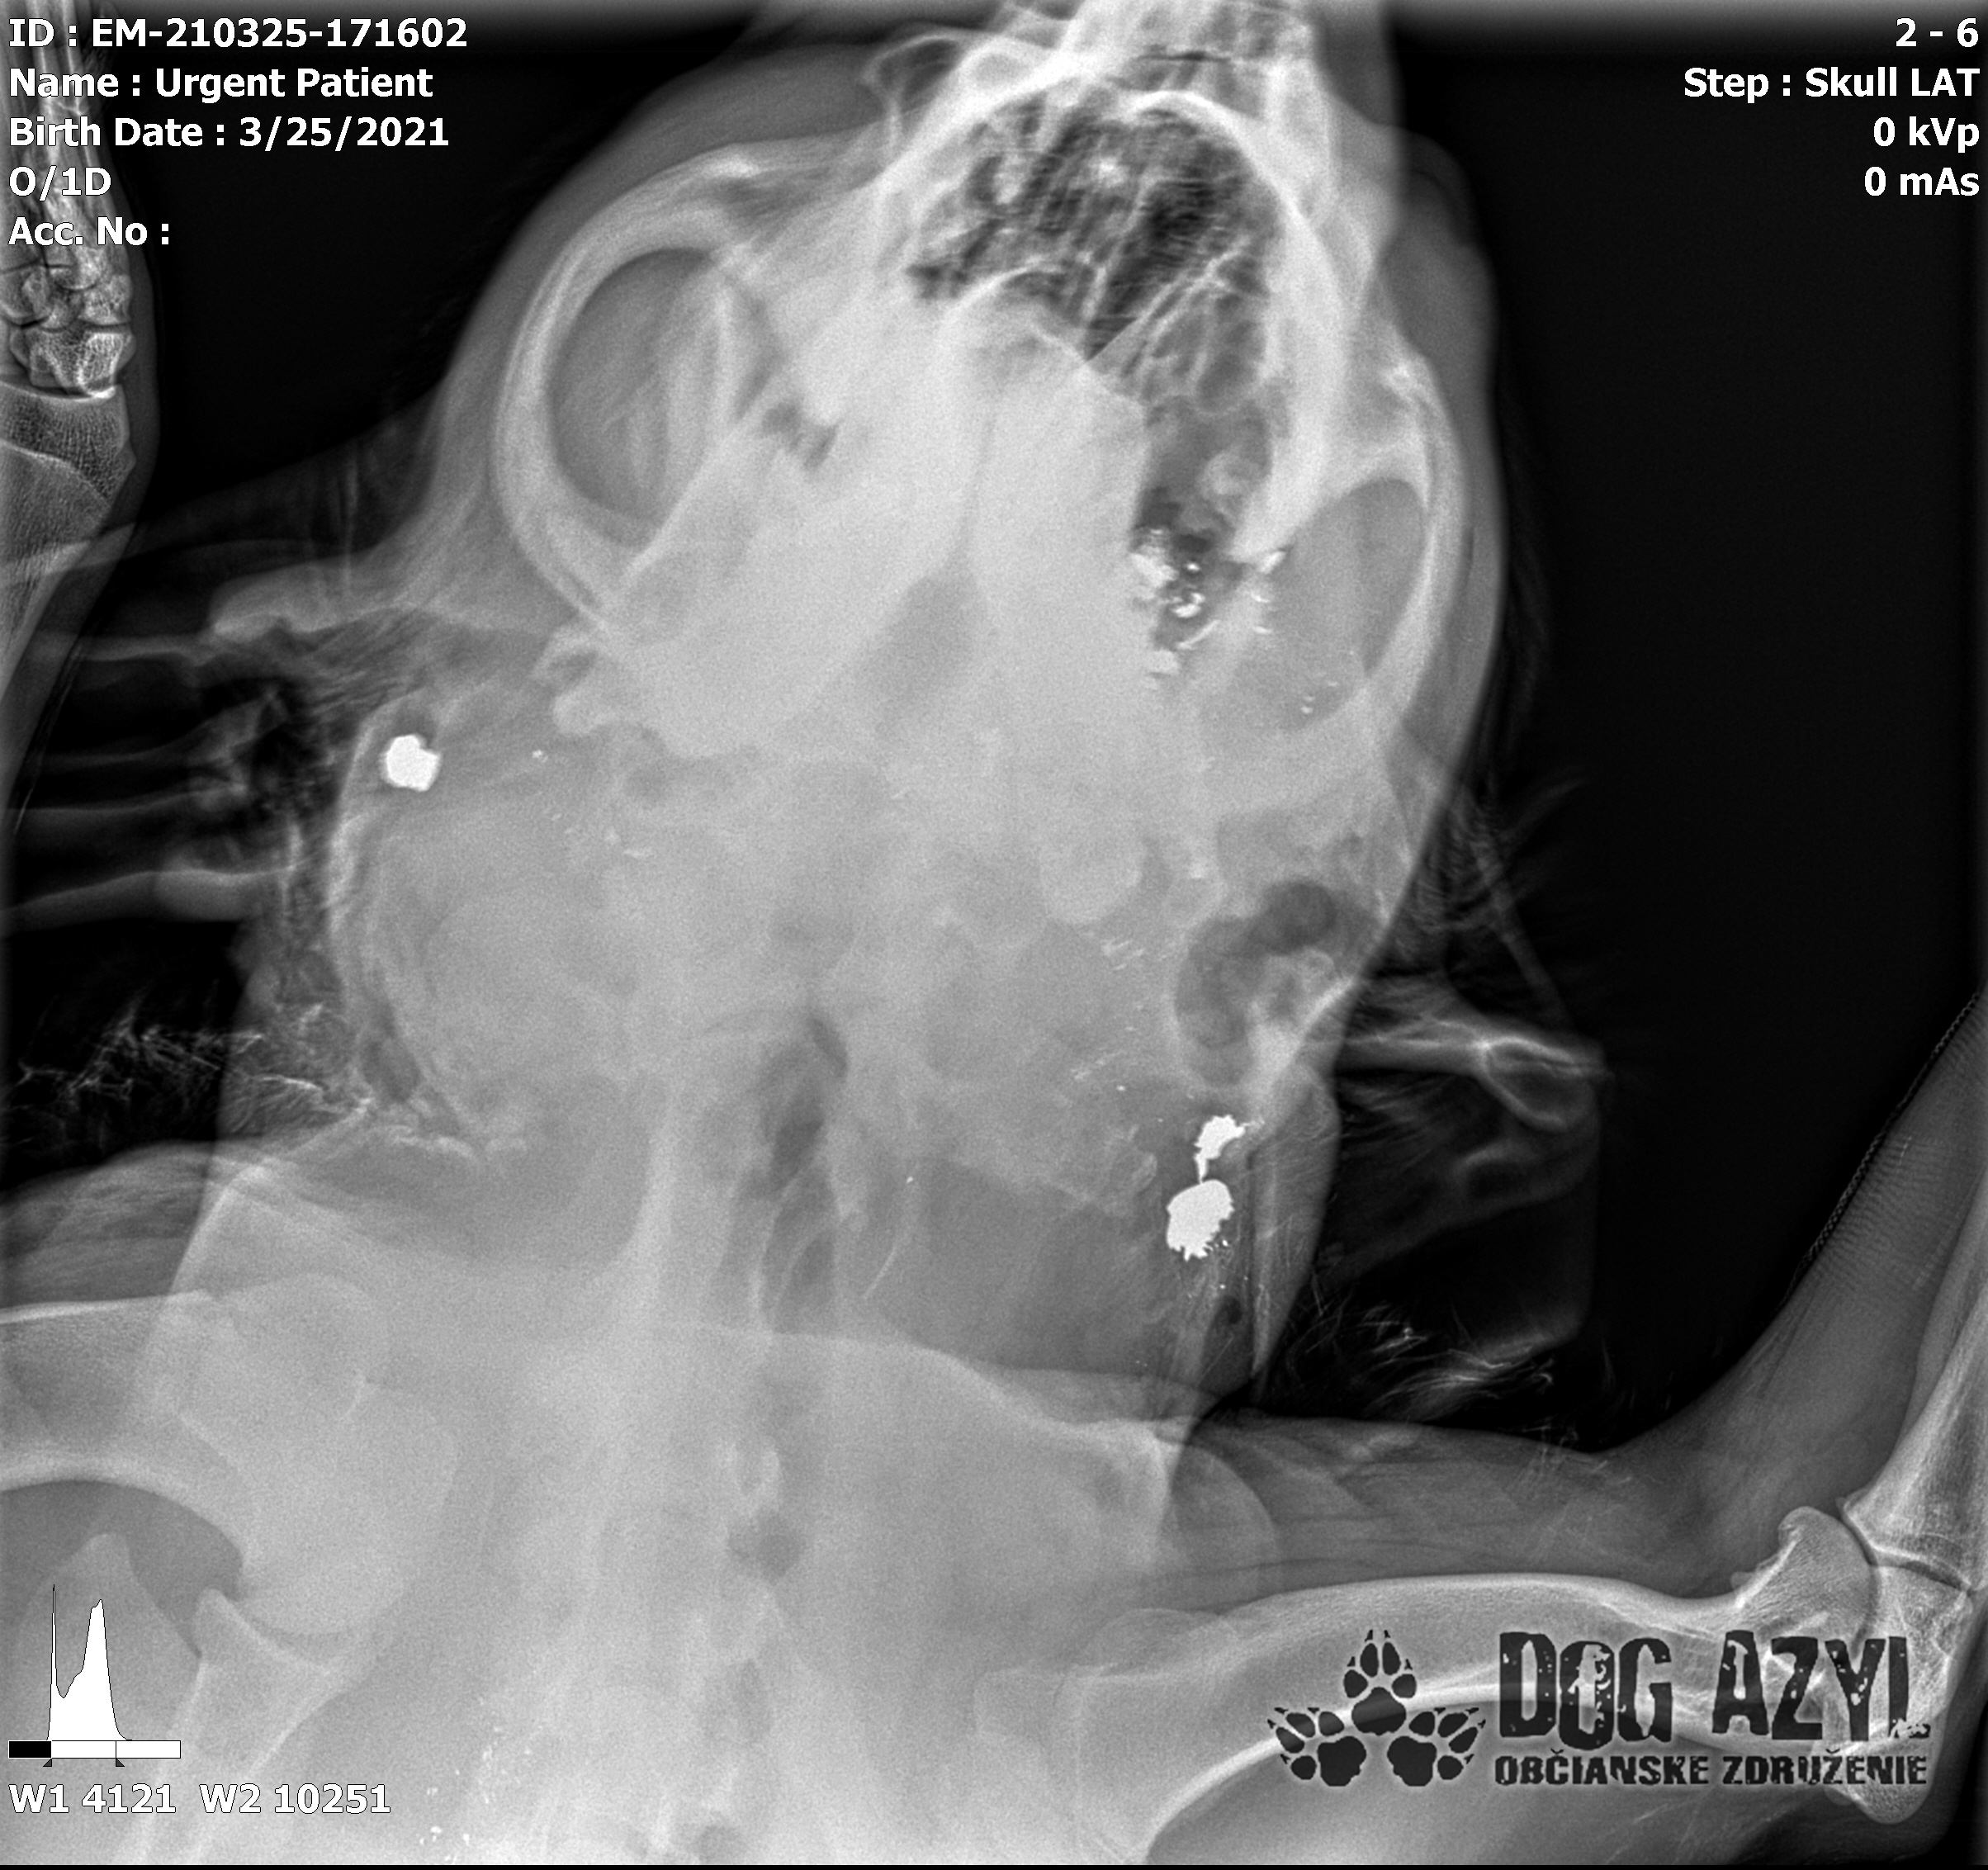

Ona ležala na ľavo, on na pravo od zavesenej šunky, ktorá mala zrejme slúžiť ako návnada, aby sa terče nehýbali.. Uprostred ničoho, bez svedkov, bez dôkazov... Pár kvapiek krvi na ceste.. Ona to schytala jedinou ranou do srdca.. On má roztrieštenú sánku, schytal to do hlavy..

/Strašne to chcem dopísať tak, aby to bolo čitateľné a pochopiteľné, ale celá sa klepem od zlosti a nevidím cez slzy.../ Lebo Ona už meno nikdy nebude mať.. On dostal meno Baris a bojuje o život!!! Má dolámanú sánku a je v šoku!!! Dostal prvú pomoc, analgetiká a priorita bola znížiť jeho teplotu z 41,4°C!!!

Ústami nevie pohnúť, jazyk si nevie ovládať a tak sa sám nedokáže schladiť ani napiť. Podľa RTG sú srdiečko a pľúca v poriadku, ale vôbec nemá vyhraté!!! Niekto chcel Barisa zlikvidovať, ale my za neho budeme bojovať do posledného dychu!!! Zajtra bude prevezený na veterinárnu kliniku Sibra centrum, kde ho čaká team špecialistov z oblasti chirurgie, neurológie a ortopédie. Ak je čo i len najmenšia nádej, že Baris bude môcť žiť, tak BARIS BUDE ŽIŤ!!!